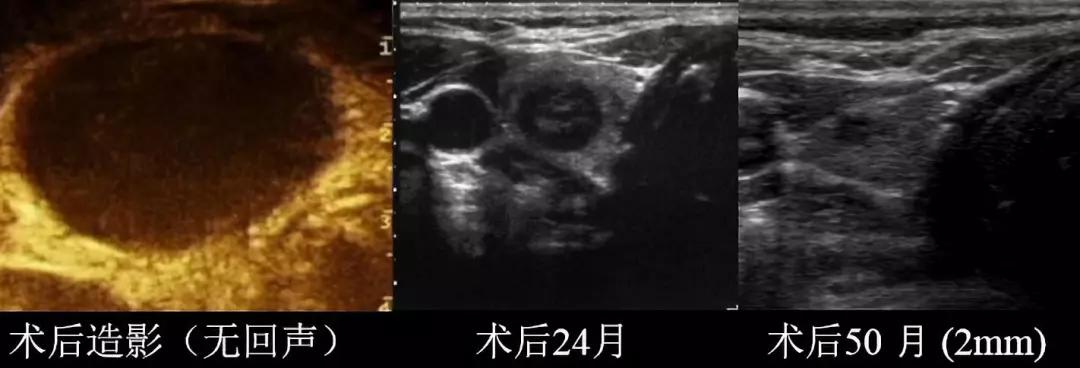

消融术后病灶“吸收”情况

(术后即刻行超声造影显示“黑洞”样,表明无活性残留,结束治疗)